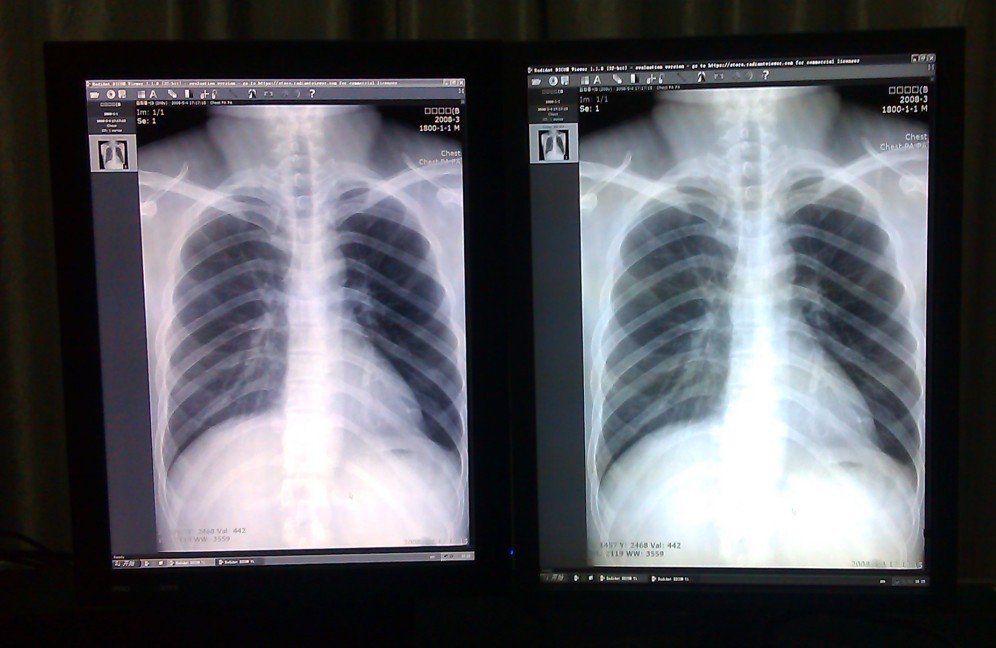

大家好!现给两个对比图给大家看下,2M灰阶显示器,左边是迈特菲,右边是日本知名品牌,比较明显,清晰度比较好,所有的设置参数都一样,但是显示效果确不一样!

显示器对比.jpg

1.jpg